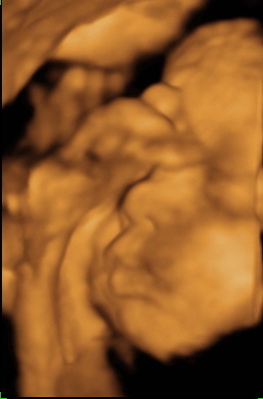

Vasárnap voltunk, bár sok dolgot nem láttunk. Kimondottan ellenzi a baba, ha meg akarjuk nézni. Engem az érdekelt, hogy mekkora lehet. Méretei alapján 1,6 kg. Ici-pici :-) Azt mondták max. 3,2-re nő meg a 40. hétig. Csöpp baba lesz. Képet nem nagyon tudott a néni csinálni, mert gombóc volt. A 20 ujjacskáját az arca elé pakolta. Kis pukkancs lett. (Hűűű, és a köldököm de fájt közben! Meg kellett kérnem, hogy inkább másfelé kalandozzunk.)

Kép

Örülnék neki, ha hamarosan megfordulna. Bár nem tudom általában mikor szoktak, de ő nagyon nem akar :(

Itt vannak azok a picike ujjak :-) Biztos ki tudjátok venni, de a bal kezecskéje kicsit közelebb van, ezért elszeletelődött :-) Hihetetlen, hogy így elférnek az emberben. Ezek a képek készültek utoljára, a legközelebbin már rózsaszín lesz!

almi